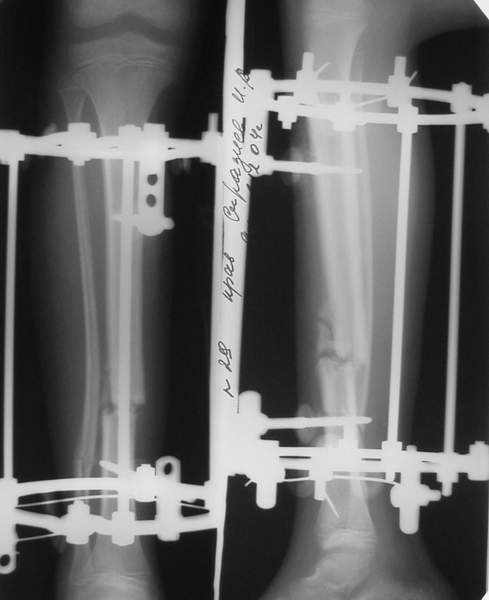

В аттачтах №№ 1 и 2 - примеры, когда 2 кольца не позволили послеоперационно

исправить смещение фрагментов большеберцовой (по ширине и вальгусное).

А казалось бы (#2) - поиграй на штангах и все влетит.

Оперировал не я

:-)